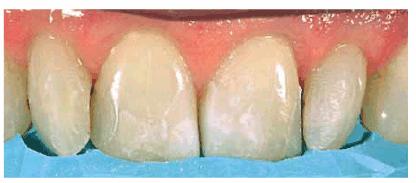

Figure 24-2A: This patient was dissatisfied with her crowded anterior teeth. Note how the gingival height differs between the central and lateral incisors.

Figure 24-2B: The dissimilar gingival heights did not bother the patient because her natural smile line concealed these irregularities.

Figure

24-2C: After a slight reproportioning of the six anterior teeth, direct

composite resin was placed and contoured (6-mm ET [Brasseler,

Figure 24-2D: The final result shows improved proportion in tooth size and form.